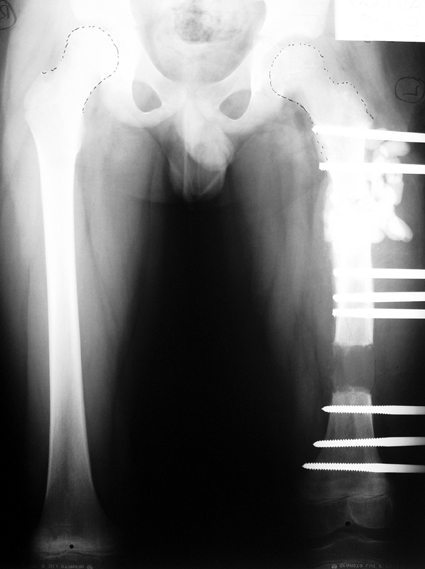

Appropriate radical debridement necessitates excision of all necrotic bone and soft tissues, and frequently causes instability at the involved extremity. The remaining bone and soft tissue defect has to be fixed and reconstructed. The distraction osteogenesis method of Ilizarov is used successfully for achievement of union, correction of the deformity, elimination of limb length inequality and reconstruction of segmental bone defects.

The duration of external fixation (external fixation index) depends on the amount of distraction required, and the extremity is prone to complications during this period. After the distraction phase is completed, the external fixator remains in place during the consolidation phase, which lasts twice as long as the distraction phase; but this period is hardly tolerated. If the external fixator is removed before sufficient consolidation is achieved, fractures, deformity and shortness will be the result. In our department, ‘lenghthening over nail’ method is used in order to decrease the external fixation index and increase patient comfort and activity level. In this method, the intramedullary nail is statically locked after the completion of the distraction phase, and external fixator is removed. The extremity is stabilized by the intramedullary nail during consolidation phase. In this way, complications due to long external fixation index or early removal of the external fixator are avoided.